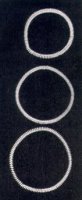

由左及右:放送格拉芬伯环的器械、格拉芬伯环样品、显示放置的格拉芬伯环的X-光照片

From the

left: Top:

Device for

inserting

the

Gräfenberg-ring,

three

samples of

the ring,

X-ray

showing

position of

inserted

ring